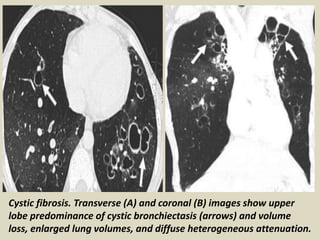

Cystic Fibrosis The most common cause of congenital upper-lung-predominant bronchiectasis

is cystic fibrosis, commonly associated with enlarged lung volumes and interstitial alterations.

An autosomal recessive genetic disorder causing ineffective clearance of secretions, cystic

fibrosis presents with recurrent pneumonias, sinusitis, pancreatic insufficiency, and infertility.

Milder forms of cystic fibrosis, however, can remain unrecognized until adulthood.

Cystic fibrosis. Transverse (A) and coronal (B) images show upper

lobe predominance of cystic bronchiectasis (arrows) and volume

loss, enlarged lung volumes, and diffuse heterogeneous attenuation.